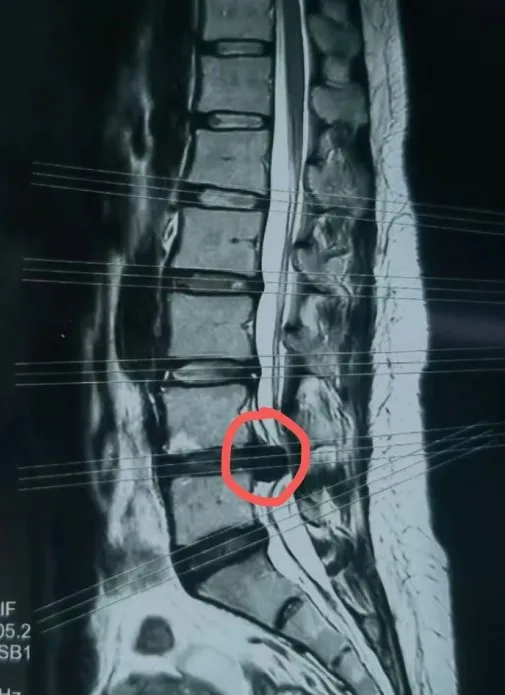

椎间孔镜手术适应症

1)椎间孔狭窄症(Ⅲ区内的椎间盘突出、关节突增生等)

2)适于各种类型的腰椎间盘突出症(极外侧型突出及脱出型、游离型、巨大型、钙化型等)

3)后纵韧带骨化症、骺环离断症

4)椎体后缘骨赘形成

5)侧隐窝狭窄症

6)腰椎管狭窄症

7)椎间盘突出、椎管狭窄伴Ⅱ度以内的稳定性脊柱滑脱,患者拒绝开放融和手术

8)开放术后复发、内固定术后引起的临椎病

9)椎间盘感染、结核、部分椎管内肿瘤、神经根囊肿等